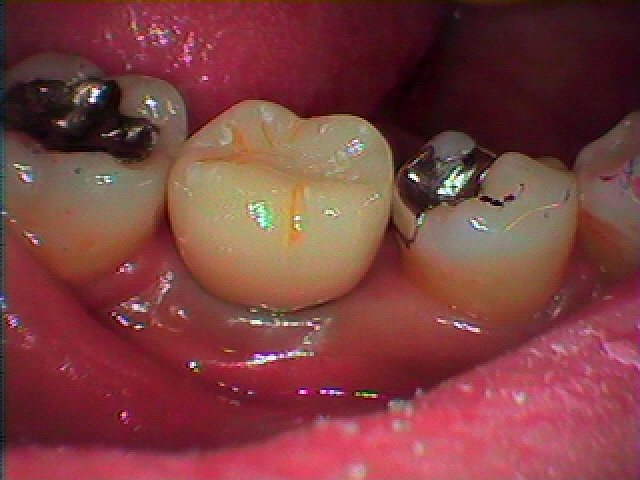

右下6番インプラント部の上部構造を作成していきます アバットメントはチタンにてカスタムオーダーにて作成し、被せはセレックオールセラミックにて作成しています

アバットメントと呼ばれる土台を立てていきました

金属が酸化しないように同種金属にて立ち上げています

セレックオールセラミックにて上部構造を作成しています

汚れがセラミックはつきにくいのとジルコニアのように割れない

マテリアルよりも、過大な咬合圧にて割れてブレーキがかかるオールセラミックをインプラントには採用しています

何十年ももつ装置がゆえにそのように作成しています